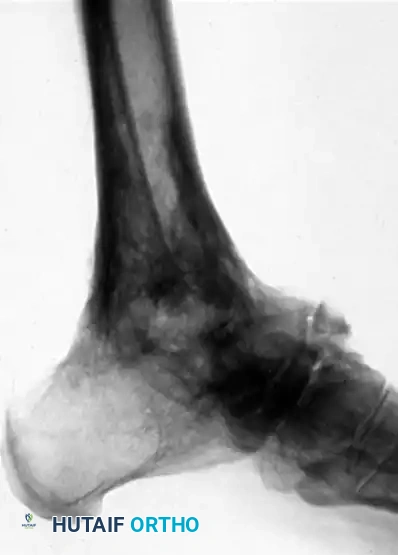

FIGURE 88-43 A: Radiographic appearance four years after tibiocalcaneal fusion achieved via compression arthrodesis and autogenous iliac bone grafting. Note the solid consolidation.

FIGURE 88-43 B: Sixteen years post-fusion. While degenerative changes at the midtarsal joints are present, the patient remains highly active with only mild symptoms, demonstrating the long-term durability of the procedure.